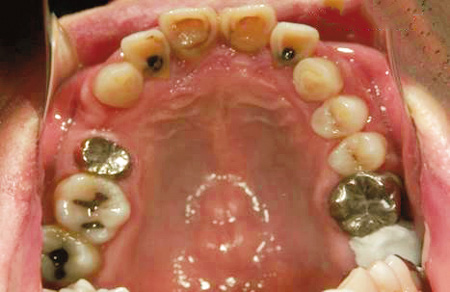

女子高校生。28歯のうち虫歯が17歯。神経に達している虫歯も多数あり。

歯垢、歯石の付着が著しく、全体に歯肉炎を起こしていた。